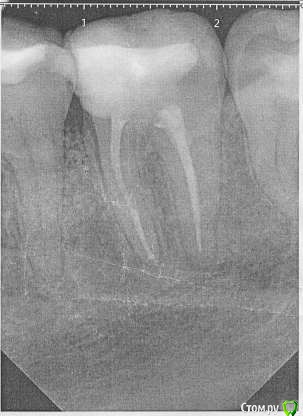

В августе прошлого года у меня начал сильно болеть десны и зуб на фоне обострения поллиноза. Врач обнаружил пульпит в болевшем зубе и еще несколько очагов кариеса по КТ. Очаги кариеса были запломбированы, в пульпитом 37 зубе было проведено депульпирование и пломбировка каналов. При пломбировке каналов врач что-то прижигал нагретой палочкой, раньше я думал, что при пломбировке использовалась гуттаперча. После лечения ощущались боли при надкусывании в 36 зубе несколько недель, на которые я не обращал внимания.

Прикладываю срезы с КТ от начала января 2017, скан распечатки прицельного снимка 36 37 зуба от ноября 2016.